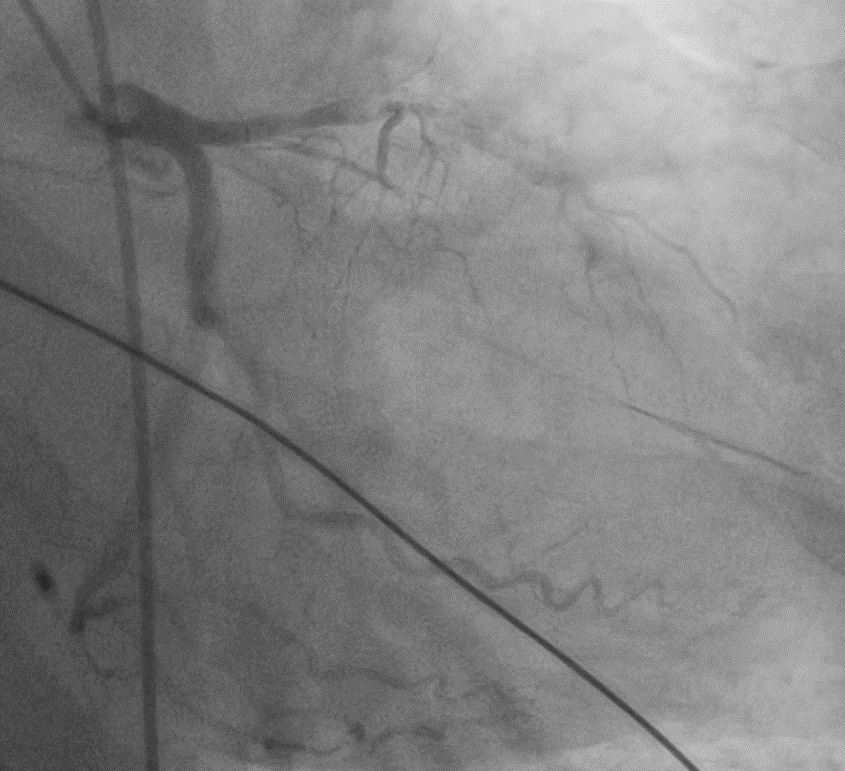

Angiogram reveals mid LAD100%, out of window period

A 65-year-old hypertensive, diabetic male presented with acute anterior wall MI (window 72 hrs) complicated by cardiogenic shock and apical ventricular septal defect (VSD) on echocardiography, showing a significant left-to-right shunt with severe PAH and EF 35%. An intra-aortic balloon pump (IABP) was inserted for hemodynamic stabilization. The procedure was performed via dual access — 6F femoral arterial sheath and 8F internal jugular venous sheath. The left ventricle was cannulated, and the VSD was carefully crossed using a catheter and guidewire, which was advanced into the pulmonary artery. The wire was then snared through the VSD defect to establish an arteriovenous loop, providing stability for device delivery. Over this loop, an Amplatzer 14 mm ASD device was advanced through the 8F sheath and positioned across the apical VSD under echocardiographic and fluoroscopic guidance. After confirming proper alignment and stability, the device was successfully released, achieving complete closure of the shunt. Immediate echocardiography confirmed no residual flow across the septum. The patient was transferred to the CCU for monitoring, with gradual IABP weaning over 4–5 days. Follow-up echocardiography before discharge showed no residual shunt, improved hemodynamics, and stable LV function.